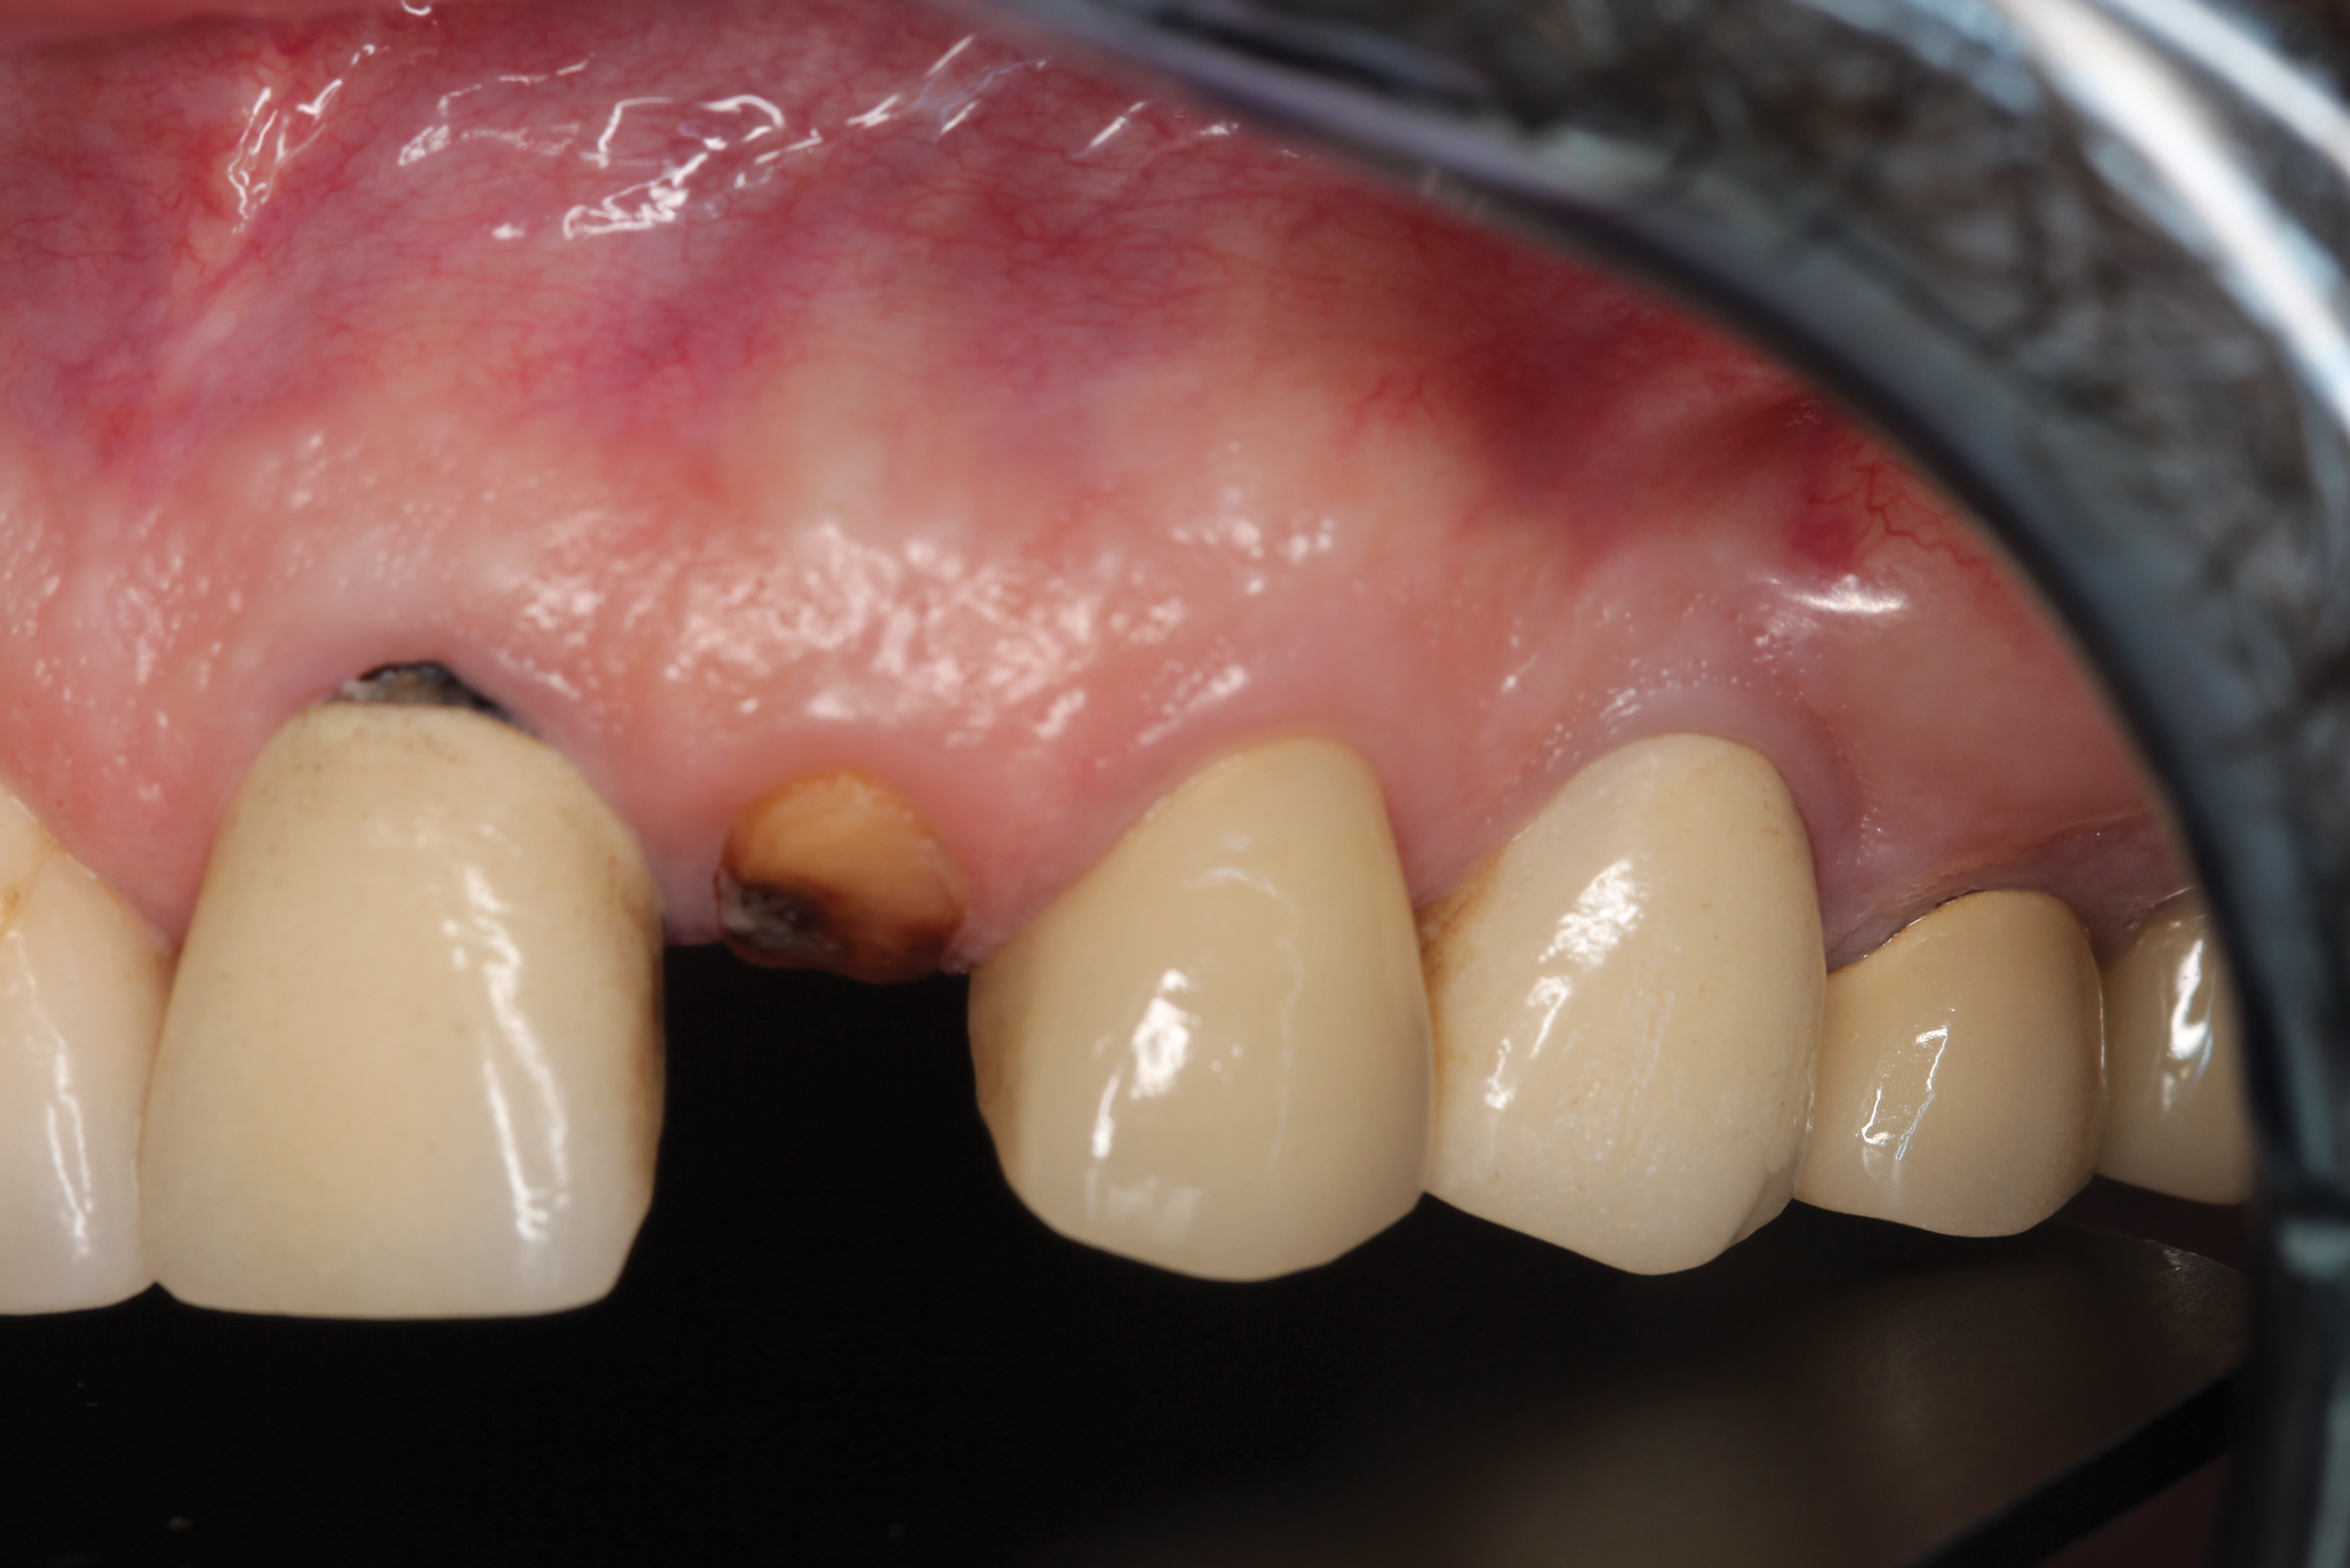

Fig 21. Soft-tissue healing after 3 months. Note maintenance of the facial gingival zenith.

Figure 21

Fig 22. Final restoration after 1.5 years. Note the soft-tissue contour on the buccal aspect.

Figure 22